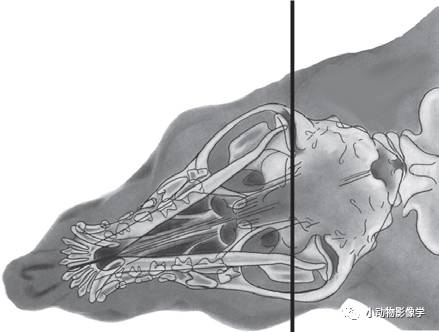

(9)颞下颌关节的拍摄

a.先拍摄标准体位DV、侧照

b.然后拍摄斜向侧照

犬:侧卧,鼻部向上或向下倾斜。一、将鼻部抬高20°,观察桌面侧颞下颌关节;二、将鼻部下压20°,使非桌面侧颞下颌关节透过对侧下颌咬肌窝投射在平板上,根据X光原理可知,这时候这一侧颞下颌关节会被放大。(参见《小动物放射诊断学》第3章)

猫:侧卧,头部向腹侧旋转20°,鼻部抬高10°,可在其它骨骼的腹侧观察到颞下颌关节。